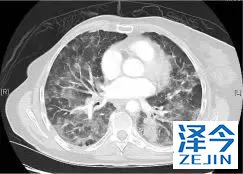

一位77岁的女性患有EPS15-NTRK1 IV期非小细胞肺癌,我们可以看到她的双肺满是病灶,并且出现了肝脏和脑转移,可以说是非常非常晚期了,

肺靶病变达到缓解,我们可以明显的看到前后的图像,病灶明显缩小了,

初始, 2018年6月 3周期 2018年8月